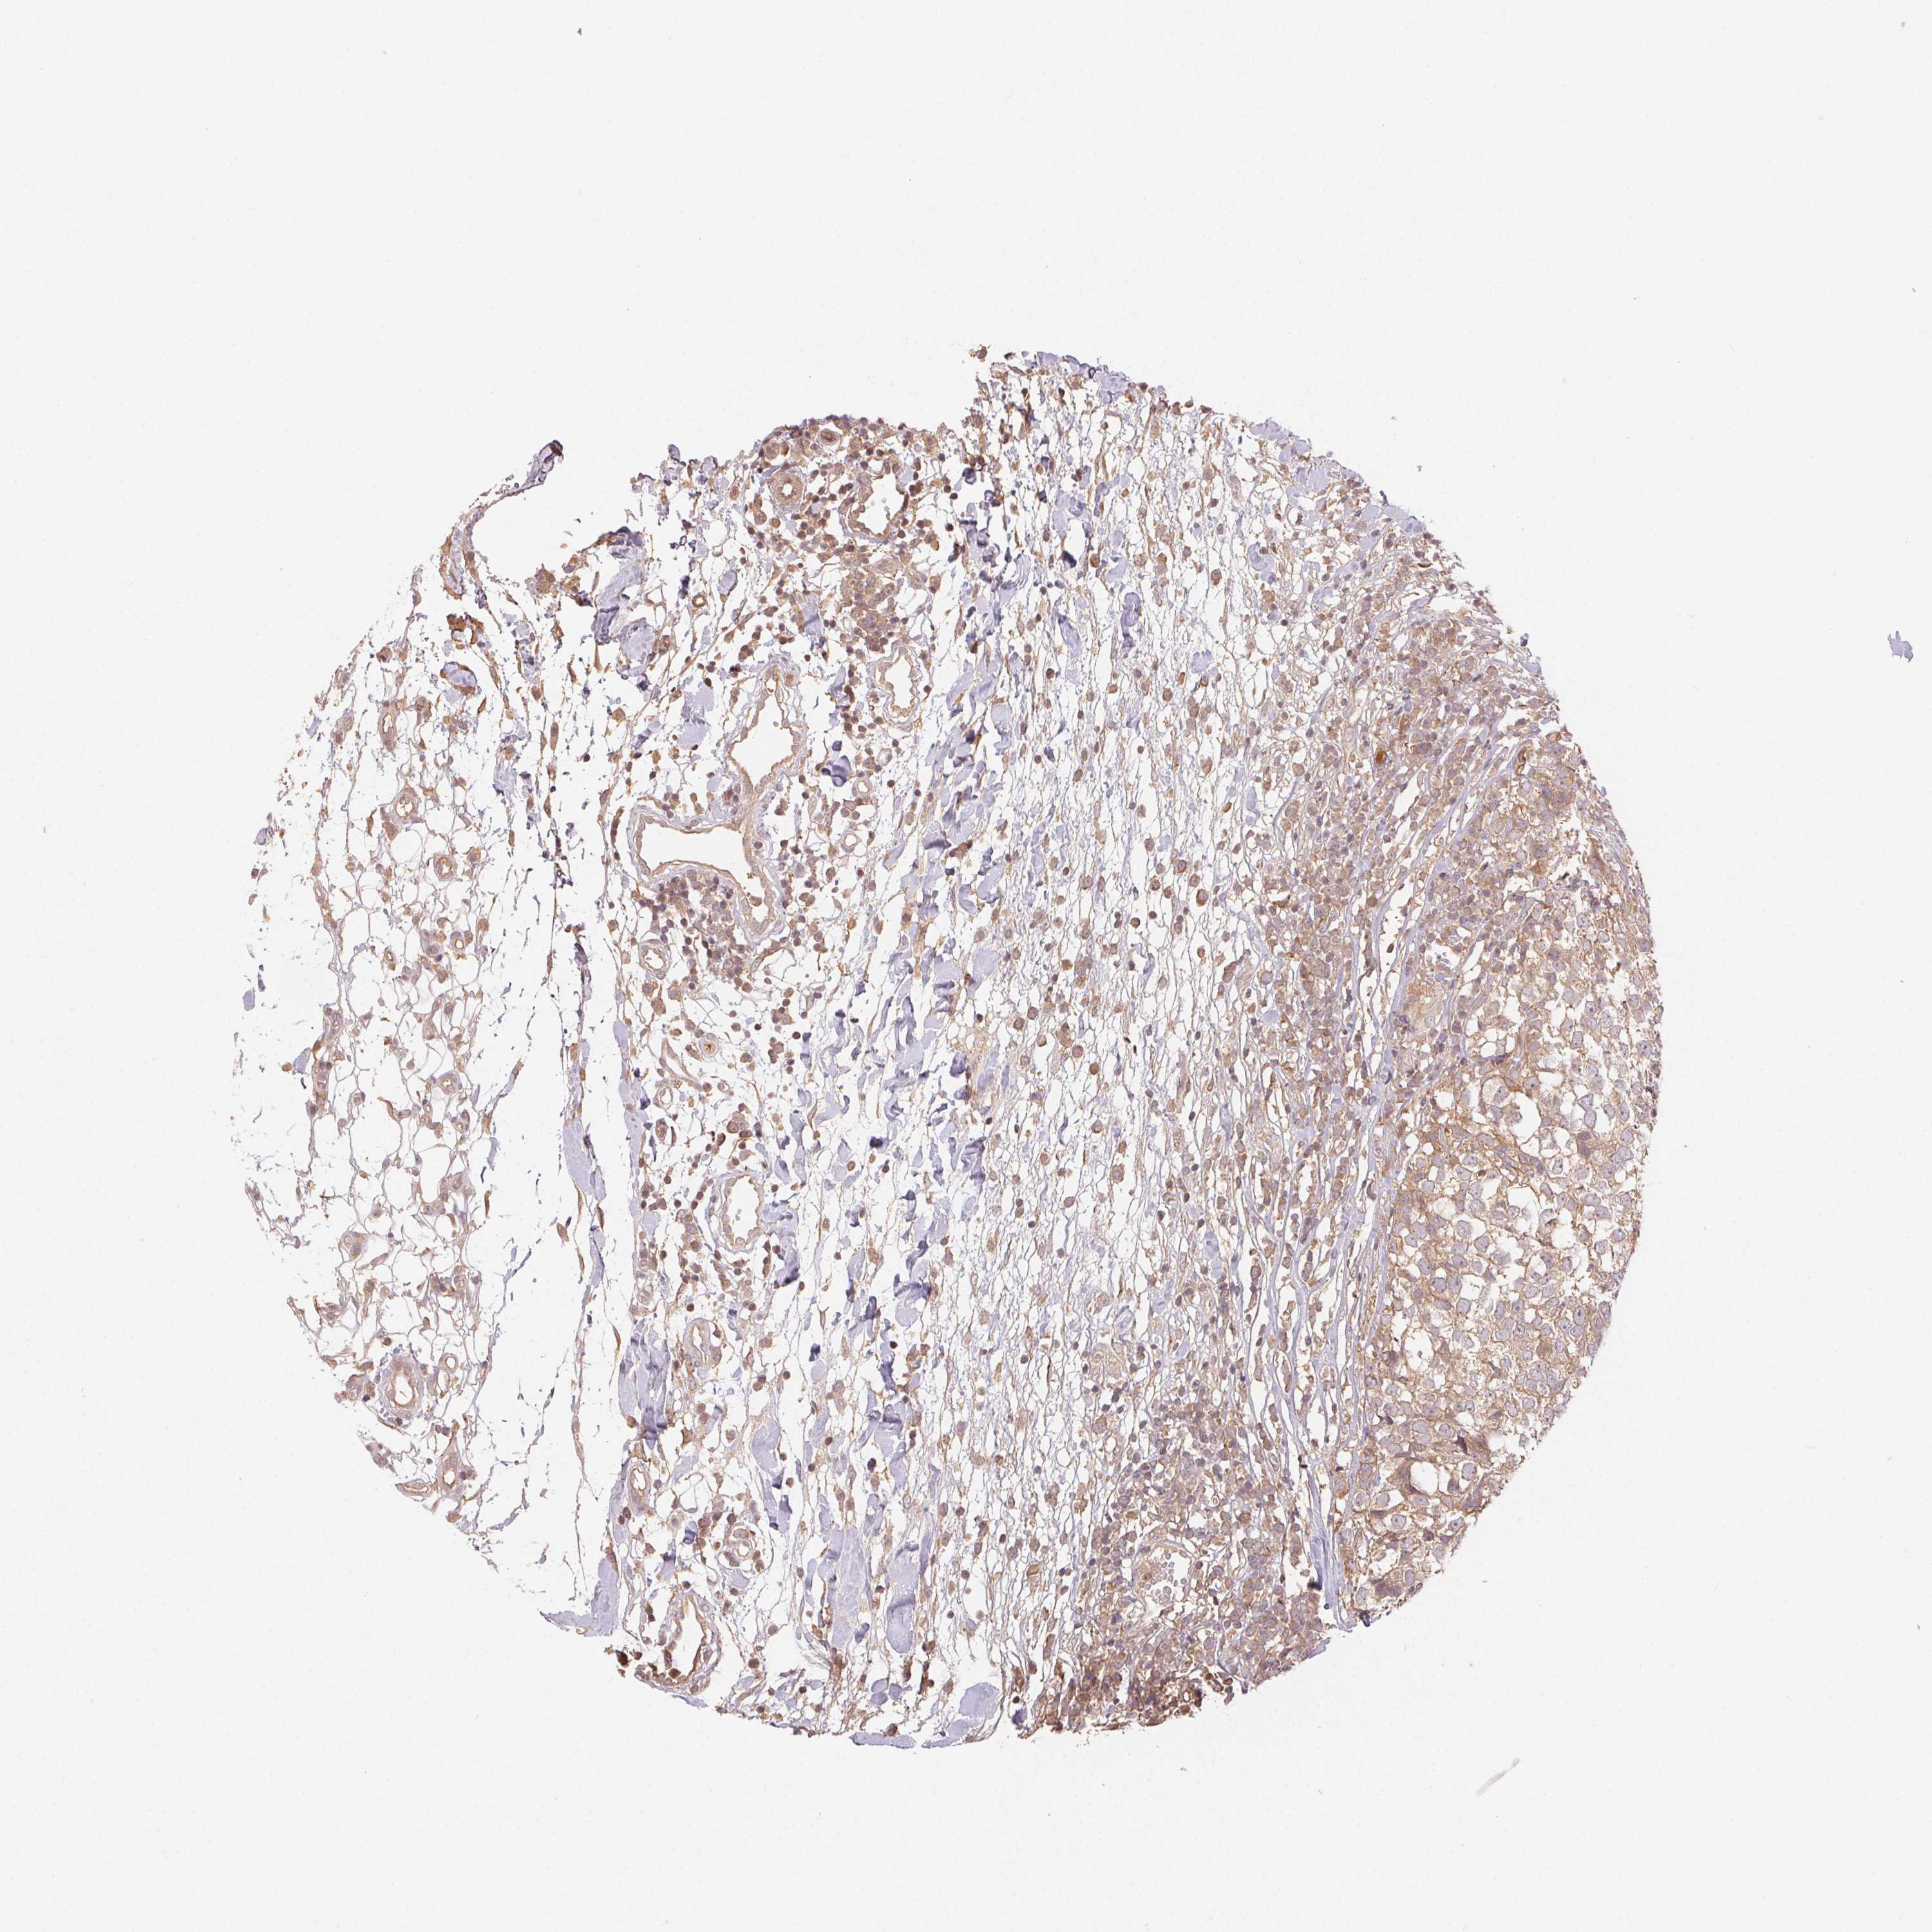

BRCA TCGA BRCA VALIDATION PROTEIN EXPRESSION

Breast cancer

Human cancer